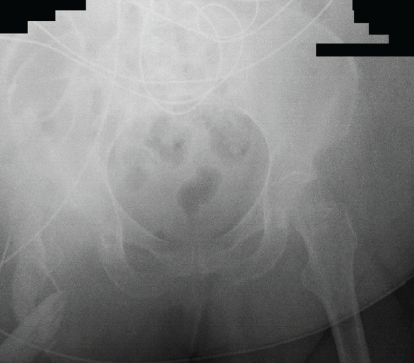

The patient returned to the ED with increased pain and purulent drainage (Fig. 5). She remained pancytopenic with platelets of 59, hemoglobin of 8.7, and elevated coagulation laboratories. The orthopedic team recommended a formal right hip I&D.

Figure 5: Anterior-posterior X-ray of the right hip upon readmission before second incision and drainage. Note the sharp spike of the greater trochanter.